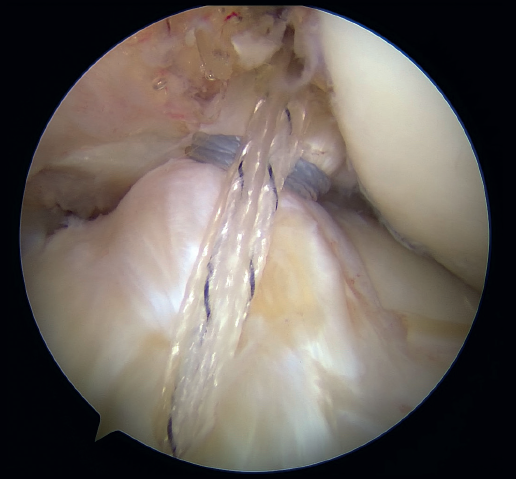

Then, and also through the cannula, arthroscopic suture forceps (KneeScorpion®, FirstPass® Mini) loaded with an ultra-high strength suture specific for this technique (FiberRing®) is introduced. Using the forceps, the suture thread is passed through the distal third of the stump of the ACL, with both ends exiting through the cannula after removal of the instrument from the joint. After removing this first thread, the steps are repeated in identical fashion with a second suture, which now passes through the ligament in a more proximal position. It is very important that these two sutures pass completely through the full thickness of the ACL.

Our attention now turns to outside the knee, where the loop of the cortical suspension system (ACL Repair TightRope®) is secured to the ACL using the FiberRing® sutures. This device is a cortical suspension button with a loop of variable length, which also incorporates a high strength tape. To secure it, the suture marked as "1" on the card is first passed through the retriever thread of one of the FiberRing® sutures, and then the step is repeated through the retriever thread of the remaining FiberRing® suture. Next, this thread passing through the rings of the FiberRing® system is passed through the closed loop marked as "2". Finally, this thread is passed through the nitinol marked "3"; the card is held firmly and the nitinol is pulled so that the TightRope® thread passes through the cortical plate. At this point, part of the loop, the button and the threads connected to it (loop traction sutures, button lift sutures and high strength tape) remain outside the knee, waiting to be inserted into the joint (Figure 8).

The next step is to remove the femoral retriever thread through the cannula of the anteromedial portal, loading it with the traction and flipping sutures, but not with the high strength tape. By pulling on the retriever thread, the ACL RepairTightRope® sutures will pass through the femoral tunnel (Figure 9), exiting through the skin. Using the lift sutures, the button is then likewise advanced through the tunnel until it is flipped over the lateral femoral cortex (which can be checked by pulling firmly on the high strength tape, which still exits through the cannula). At this point, all that remains is to pull alternately on both loop traction sutures to shorten the loop and reduce the stump of the ACL until contact is made with its native footprint.